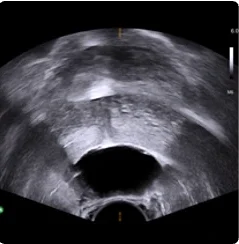

Procedural scan showing placement of the BioProtect Balloon Spacer in a salvage case. Saggital view.

Saggital Ultrasound

Image courtesy of Dr. Stan Golin, Radiation Oncologist.